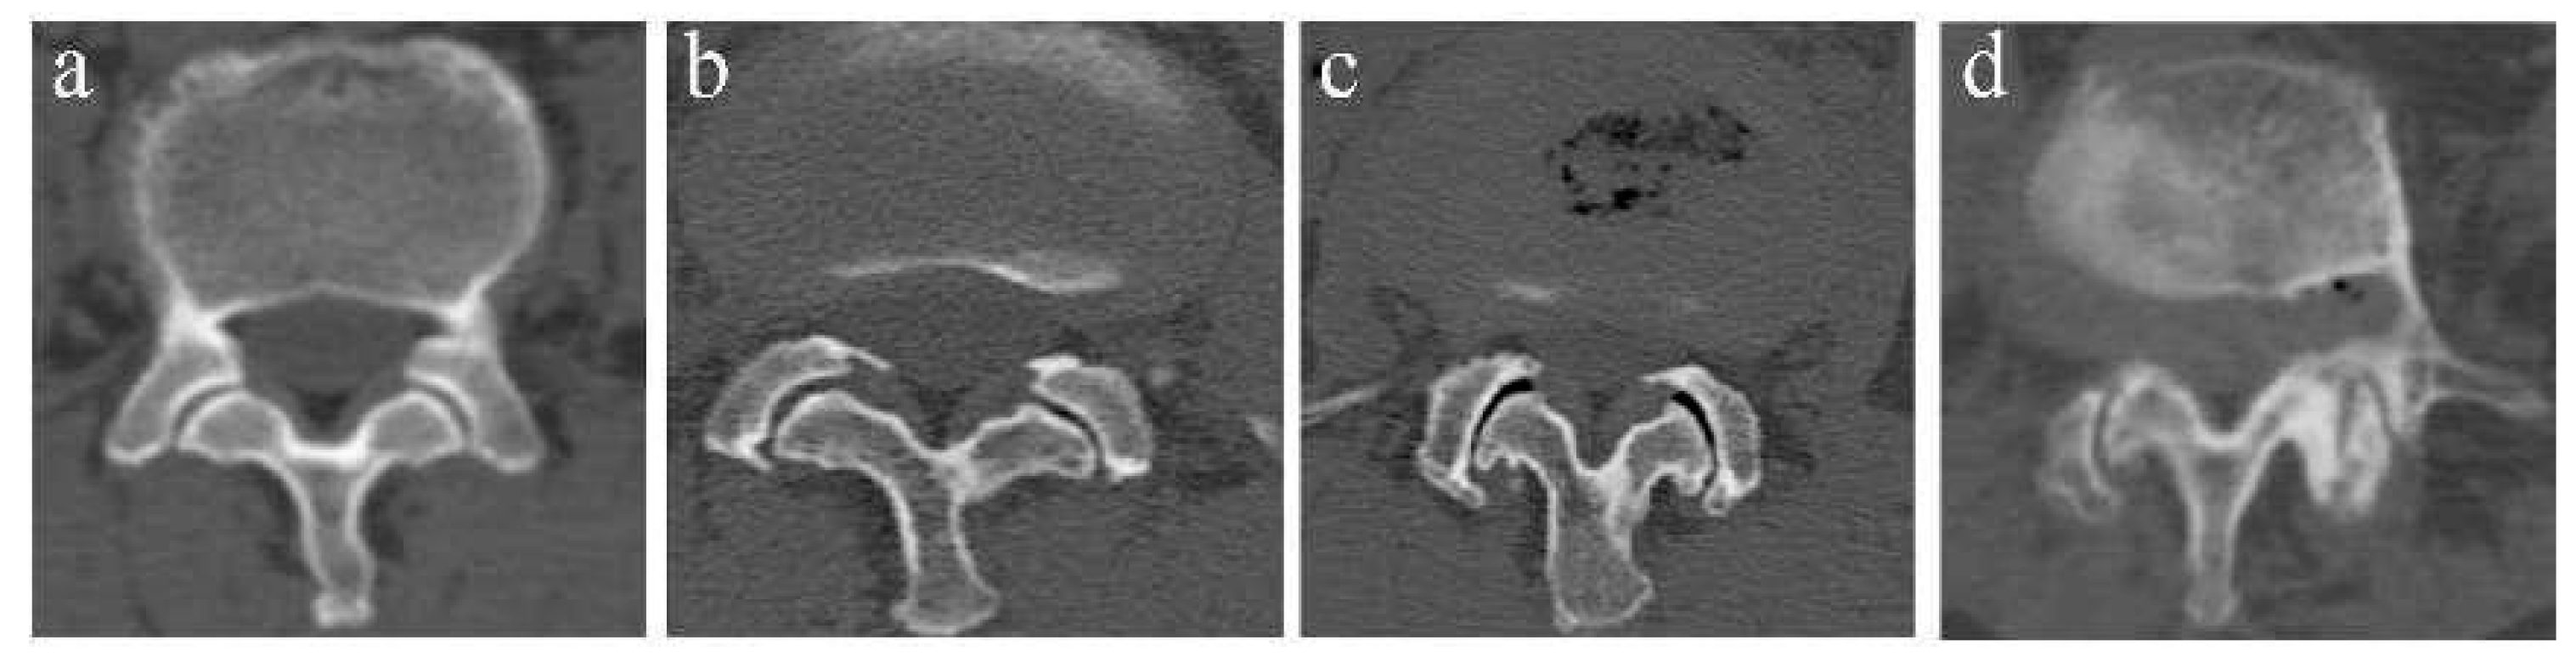

The FJOA was classified into 4 grades via the criterion of Pathria et al. [10] on CT. Grade 0 corresponds to a normal facet joint and grade 3 corresponds to a severely degenerated joint (Figure 3).

Figure 3.

Example of FJOA on CT. (a) Grade 0: normal facet joint. (b) Grade 1: mild osteoarthritis facet joint with narrow space and small osteophytes. (c) Grade 2: moderate osteoarthritis with sclerosis or subchondral erosions. (d) Grade 3: severe osteoarthritis with marked osteophyte.